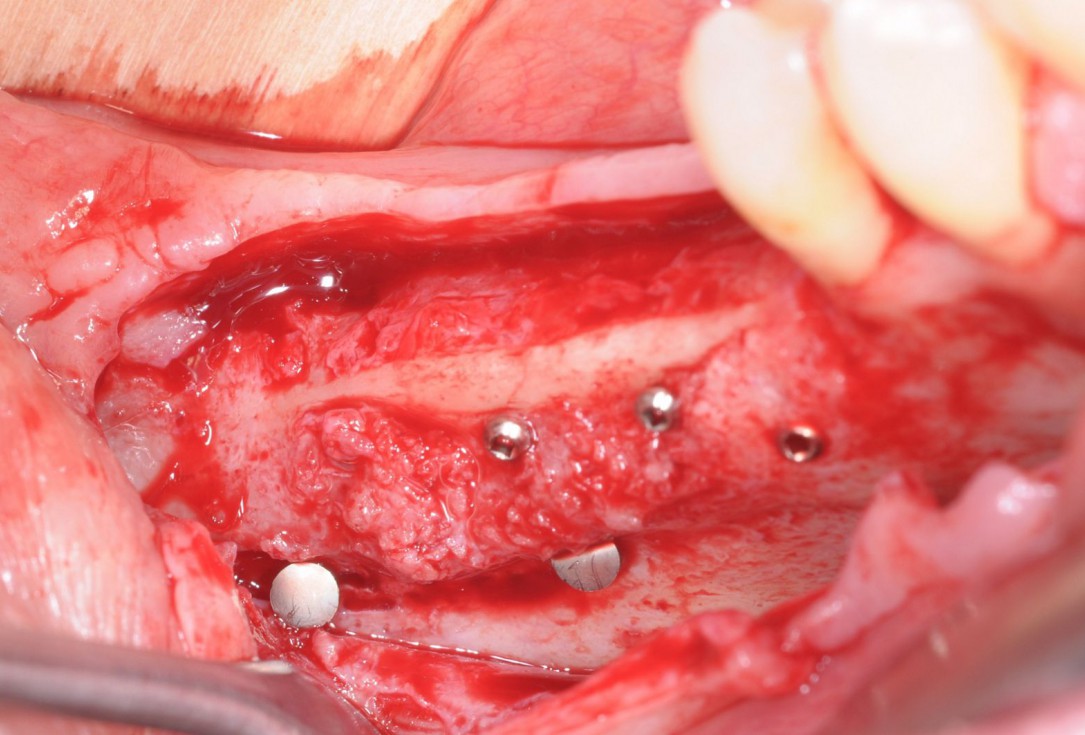

17/28 - Excellent osseous integration of the allogenic cortical plates with new bone attached to the outside and optimal bone tissue regenerationThree-dimensional augmentation with maxgraft® cortico - Dr. R. Würdinger